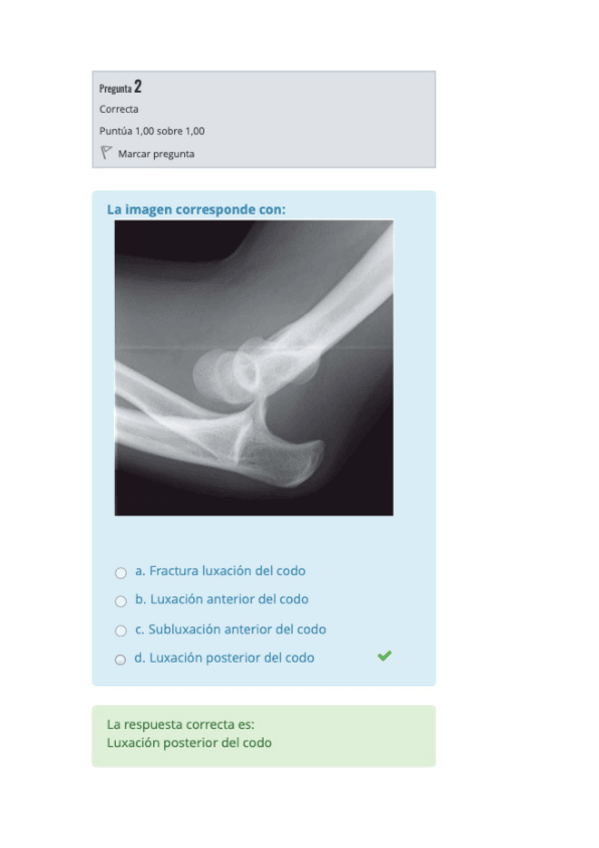

Soluciones de la 2ª práctica de musculoesquelético del curso 25-26

2 páginas